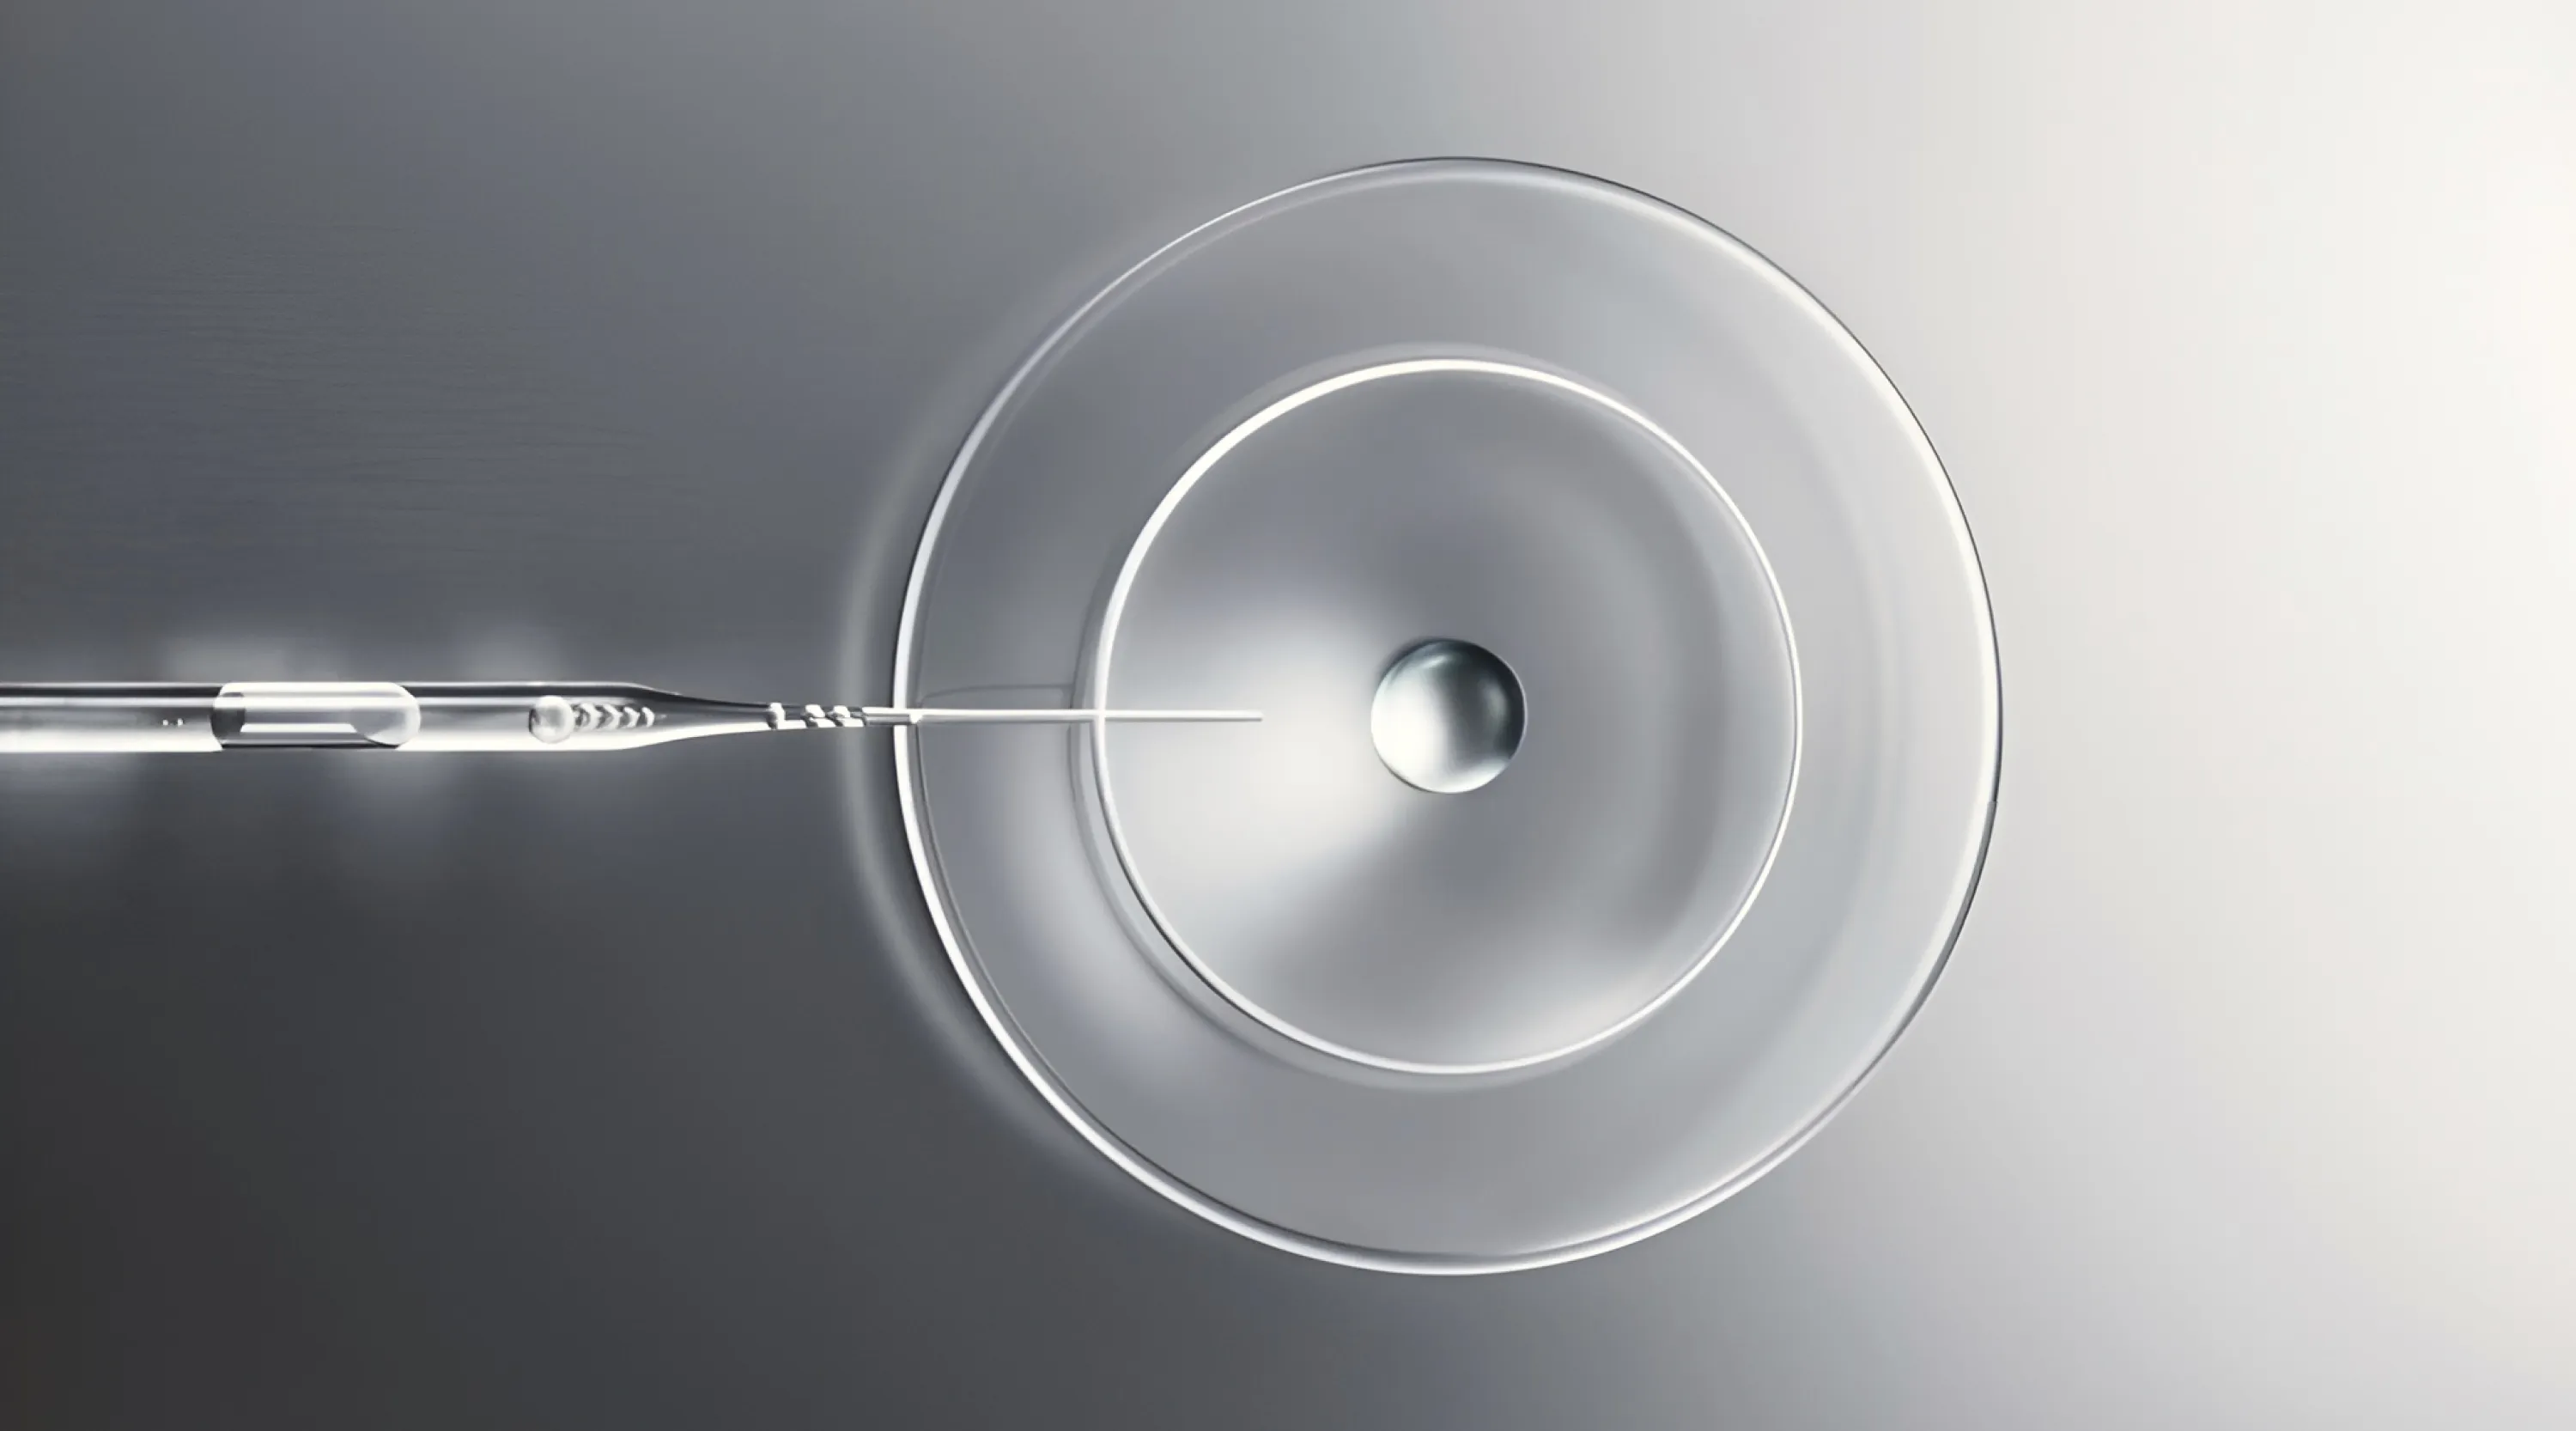

Применение технологии «Скаффолд» в инновационных техниках работы со сложно корректируемыми зонами лица

- Технология «Скаффолд» в препаратах Contoura Bio.

В чём суть и отличительная особенность технологии.